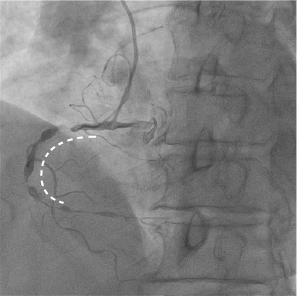

最终CAG和IVUS

术后造影及IVUS可见支架膨胀及贴壁良好,支架远近端未见夹层血肿。